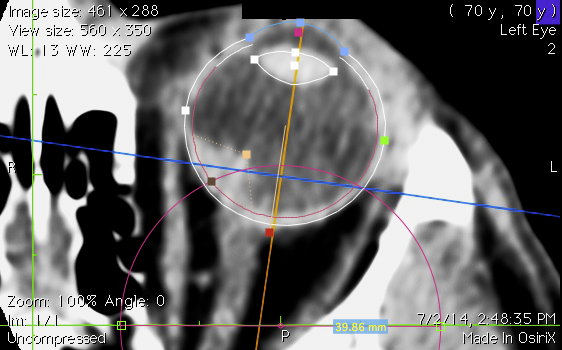

Axial CT Reconstruction

• Open the axial multiplanar reconstruction (MPR) created in OsiriX.

• Calibrate the image (e.g. 40 mm).

• Adjust the eye modeling tool to fit the eye.